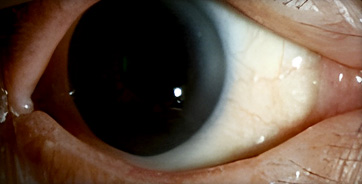

눈동자를 덮고 있는 결막이 탄력을 잃고 늘어지면서 주름이 생기거나 안구 밖으로 밀려나와

눈동자와 눈꺼풀 사이가 부어오른 것처럼 눈꺼풀을 덮이는 것이 특징으로, 눈이 자주 시리고 이물감이 느껴지며

눈물이 수시로 고이거나 흘러내린다면 결막이완증을 의심해 볼 수 있습니다.

치료 전 늘어진 결막

아큐트론 치료 후

※ 환자의 이해를 돕기 위한 예시 이미지이며, 시술 결과는 개인차에 따라 다를 수 있습니다.